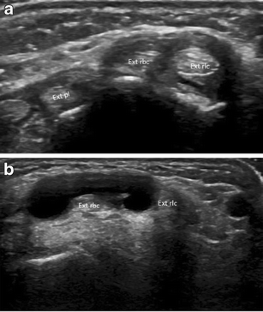

Intersection syndrome: ultrasound imaging

Intersection syndrome was identified in 1.9 % of all patients evaluated in the setting of a specialized hospital. Ultrasound is a non-invasive, simple, and economical method for the identification of intersection syndrome, tendon sheath anatomy (individual or separate sheaths) and to exclude other pathological conditions.